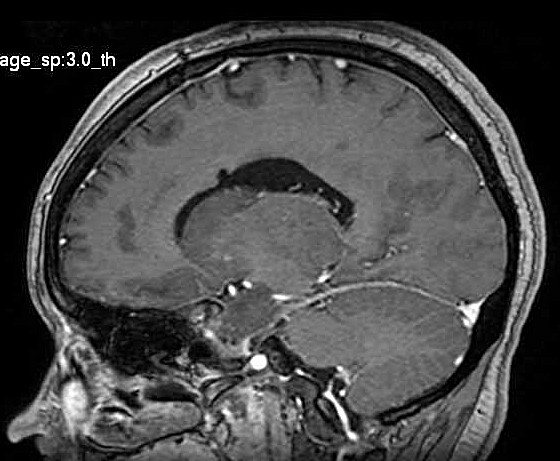

| Fem. 17a. |

| Nódulo sólido homogêneo preenchendo o III ventrículo, com limites precisos, com hipossinal em T1 e hipersinal em T2 e FLAIR, que se impregna por contraste paramagnético. Lesão menor implantada no assoalho do IV ventrículo provavelmente representa disseminação por via liquórica. |

| SAGITAIS, T1 SEM CONTRASTE | T1 COM CONTRASTE | |

| F. 17a. Tumor teratóide rabdóide atípico de III ventrículo. RM | HE | VIM, GFAP | HHF35, desmina, 1A4 | AE1AE3, EMA |